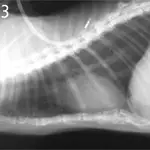

A lateral radiograph of a canine thorax shows the rib cage, spine, and heart silhouette, with clear visibility of the lung fields. The image highlights potential abnormalities such as fluid accumulation or masses within the thoracic cavity.

Figure 3. Thorax of a cat with intestinal adenocarcinoma(lateral view). Note the gas opacity caudal to the diaphragm (black arrows) that shows a separation of the diaphragm and liver (white arrow).